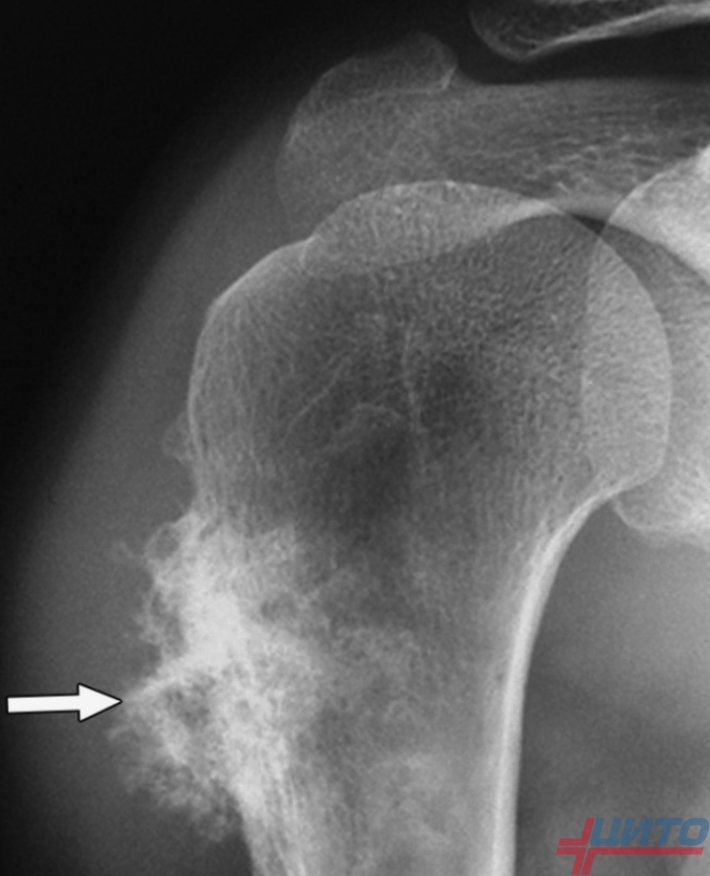

Рентгеновские снимки саркомы плечевого сустава